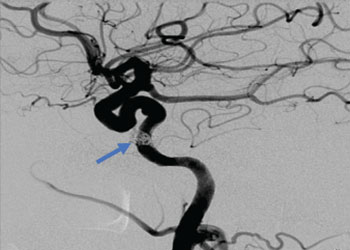

Endovascular:

CME:

Symptomatic Near-Occlusion of the Carotid Artery

Author: Jonathan L. Brisman M.D., F.A.C.S., Read More!